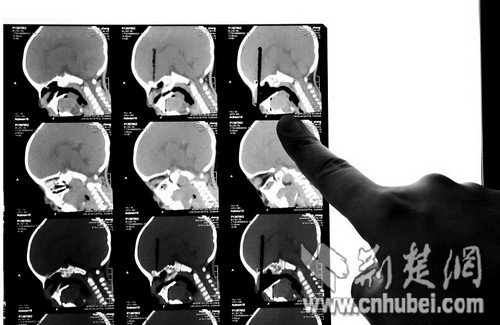

????圖為:CT掃描顯示筷子插入顱內(nèi)8厘米

????當(dāng)時(shí)接診的是該院神經(jīng)外科主治醫(yī)師雷德強(qiáng)博士,他說(shuō):“當(dāng)時(shí)成成神智尚清,四肢可以活動(dòng),但出現(xiàn)精神差、嗜睡、間歇性哭泣的反應(yīng),鼻腔還有血液流出?!苯?jīng)過(guò)3D的CT掃描,醫(yī)生們發(fā)現(xiàn),一次性筷子由鼻腔經(jīng)過(guò)篩竇插入孩子顱內(nèi),顱內(nèi)長(zhǎng)度近8厘米,在鼻腔內(nèi)大概有三四厘米,情況危急,需要立即手術(shù)。